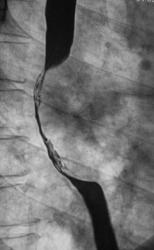

Линейные томограммы в прямой проекции

По представленным снимкам, у меня сложилось впечатление что пищевод как бы сдавлен извне (овал), возможно образованием в заднем средостении; при этом на довольно продолжительном участке есть нарушение архитектоники складок слизистой с множественными участками barium depletion (стрелки), свидетельствующими в пользу изъязвления.

Выводы: изначально хотелось бы узнать анамнез и жалобы; но так как их не представлены, буду рассуждать опираясь только на семиотику. У меня 2 варианта: опухоль пищевода с преимущественно интра-муральным ростом или образование средостения с прямой инвазией пищевода вплоть до слизистой оболочки, в данном случае может быть много вариантов. Моя рекомендация-конечно КТ, посмотреть стенки пищевода и окружающие структуры.

Исходя из вышесказанного, по данному случаю: сдавление просвета и смещение пищевода мягкотканным образованием, выходяшим за пределы стенки, изъязвление передней стенки пищевода. Заключение: подслизистая опухоль пищевода с изъязвлением, вероятнее всего лейомиома. Рекомендации: эндоУЗИ с биопсией, КТ.

После проведенного рентгенологического исследования органов грудной полости - рентгенографии и томографии, при которой были выявлены увеличенные лимфатические узлы в корнях лёгких и средостении, было проведено рентгенотелевидение пищевода с прицельной рентгенографией и исследованием пищевода на трохоскопе, с контрастированием пищевода водной взвесью сернокислого бария "различной консистенции" - от сверхжидкого - до пастообразного, для "выяснения состояния" заднего средостения. Была зарегистрирована и документирована "локальная деформация пищевода" на протяжении 9,5 см. с перестройкой структуры "рельфа слизистой оболочки".